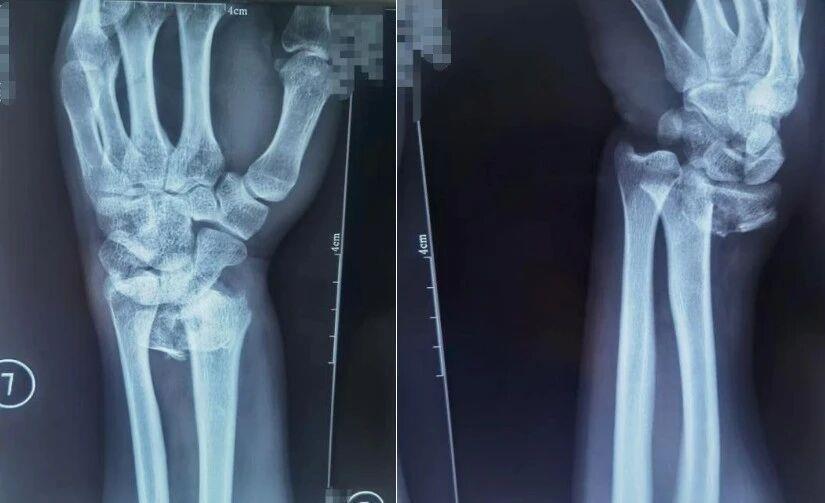

桡骨远端骨折

跌倒时用手腕撑地是常见的自我保护动作,但这一动作极易导致桡骨远端骨折,表现为手腕肿胀疼痛、活动障碍,严重时还会出现明显畸形。

患者桡骨远端骨折,图为复位前正位、复位前侧位。图源:哈尔滨骨伤科医院